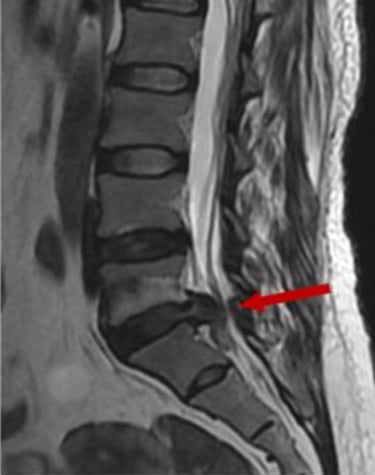

Tipo de hernia: las hernias extruidas o secuestradas (cuando el material se ha desplazado fuera del disco) tienen mayor probabilidad de reabsorción, ya que el sistema inmune puede acceder más fácilmente a ese tejido.

En cambio, las protrusiones discales (cuando el disco solo se abomba sin romperse) tienden a ser más estables y menos propensas a reabsorberse, aunque también pueden mejorar clínicamente con tratamiento conservador. El siguiente dibujo muestra la probabilidad de reabsorción según el tamaño de la hernia.